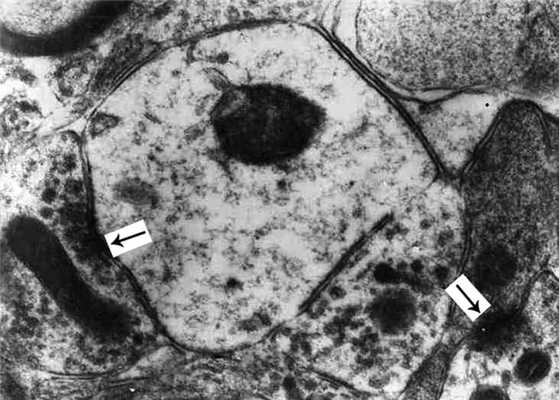

Рис. 6. Крупная нейросекреторная клетка из СОЯ. Яд - ядрышко, стрелкой обозначены нейросекреторные гранулы. Ув. 3000.